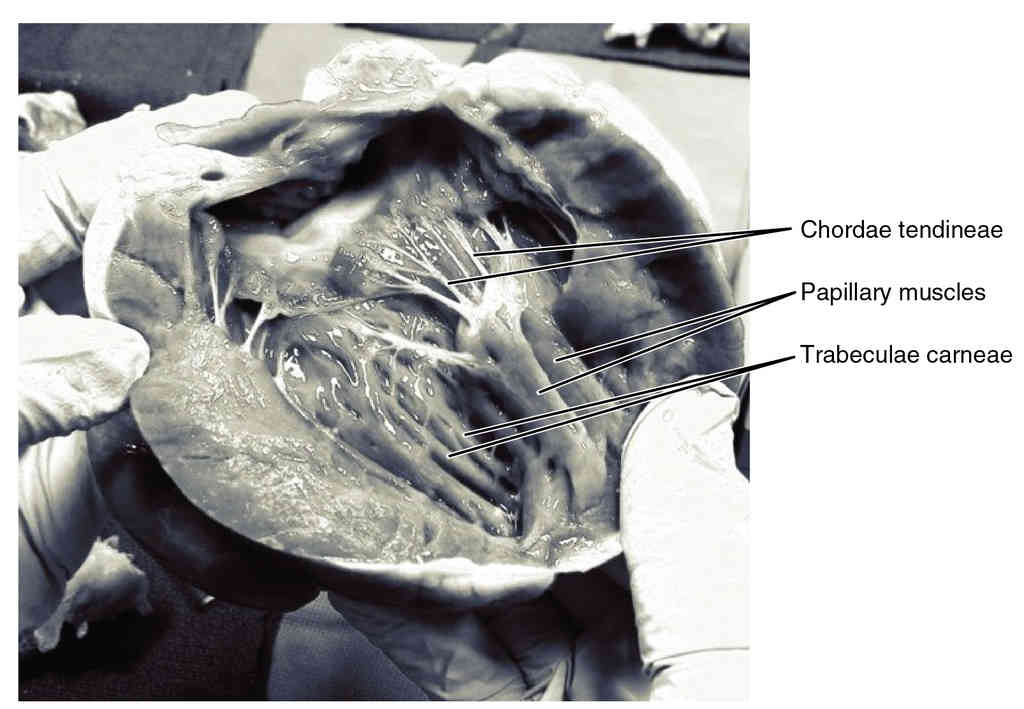

This page is under construction. For now, it is just a resource of the images found in the OpenStax Anatomy and Physiology Handbook. It wil slowly change into a revision tool. Each slide has a number. Use this to refer to the slide. When completed, it will have an unlabelled section, with labelled slides in parallel. On the unlabelled slides, write your answer and use the labelled slide to assess yourself. Keep track by also noting the number on each slide. Improvement at each attempt is important, more so than full marks on a first attempt.